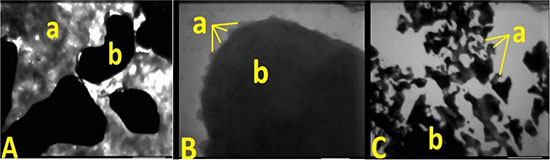

The test of sodium dodecyl sulfate-polyacrylamide gel electrophoresis showed that the new tracers were positive results (Figure 1). The test of enzyme linked immune sorbent assay showed that the new tracer kept the immune activity of Rituximab. The scanning electron microscopy image of the new tracer was showed in Figure 2.

Figure 2: Scanning electron microscopy image of the new tracer, ICG (a) combined with the Rituximab (b). (A) is the combination ratios of 1:3, (B) is the combination ratios of 1:4, and (C) is the combination ratios of 1:12, 1:16, and 1:32. There are many uncombined ICG found in A and sediments observed in C.

ICG has a character of low photo-stability and thermal stability [34, 35]. The studies about the stability showed that ICG would decompose and produce singlet oxygen when exposed to light [36, 37]. We used this character to identify ICG combined with Rituximab and on the surface of the antibody. When the narrow focused high energy electron beam in the vacuum environment of the scanning electron microscopy focused on the surface of the new tracer about 30 seconds, the ICG-Rituximab released some gases which were production of ICG. The scanning electron microscopy image of ICG-Rituximab showed that many uncombined ICG were found in combination ratios of 1:3 and sediments in 1:12, 1:16, and 1:32 (Figure 2). The sediment and the free ICG were not found in 1:4 (Figure 2), so the appropriate combination ratio of ICG and Rituximab might be 1:4. We performed further study to this combination ratio ICG-Rituximab. In the biological property study, Rituximab was combined with ICG efficiently and retained biochemical integrity, stability and biological activity in the combination ratio of 1:4 ICG-Rituximab. After identifying no bacteria existence and no pyogen of ICG-Rituximab, the toxicity test was done in mice. The acute toxicity test showed no mouse died and the local toxicity test found no skin reaction and no allergic reaction. While the standard dose of Rituximab recommended for the treatment of lymphoma is 375 mg/m2 for patient [38, 39], the dose of the new tracer used for SLNB is just 1/1000 of the therapeutic dose and the administration route has changed from intravenous injection to local injection. Thus, it is safe for the human body with local injection of ICG-Rituximab. Also, no toxicity had been found in the clinical studies of ICG (ICG-99mTc-nanocolloid) and rituximab (99mTc-carbonyl-DTPA-Rituximab and 99mTc-nanocolloid-Rituximab) for SLN imaging [23–27].